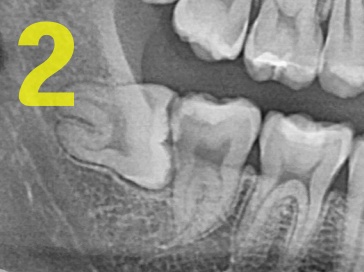

② 복잡 매복 : 치조골에 2/3 이하로 묻혀있을때 (사진2)